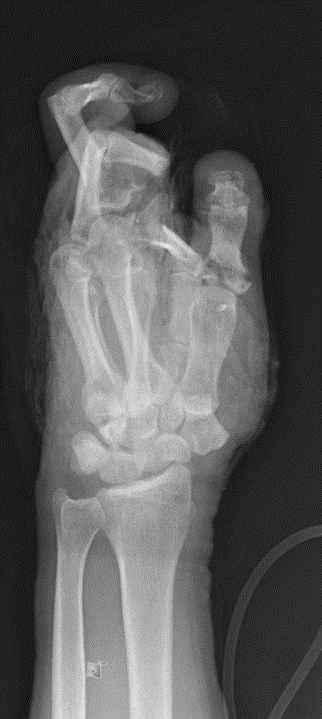

Der Knall, der bleibt: Warum Feuerwerksunfälle medizinisch besonders komplex sind

Wenn in der Silvesternacht Raketen den Himmel erleuchten, ist das für viele ein besonderer Moment. Ein Innehalten vor einem Jahr voller neuer Möglichkeiten. Doch wenn der Umgang mit Feuerwerk schiefgeht, kann dieser Neubeginn eine andere Richtung nehmen. Zwei Chirurgen der BG Unfallklinik Murnau, dem größten überregionalen Traumazentrum im süddeutschen Raum mit zertifiziertem Schwerbrandverletztenzentrum, geben Einblick in ihre medizinische Sicht auf diese Nacht: Dr. Markus Öhlbauer, Chefarzt der Plastischen Chirurgie, und Dr. Nils Baas, Chefarzt der Hand- und Unterarmchirurgie.